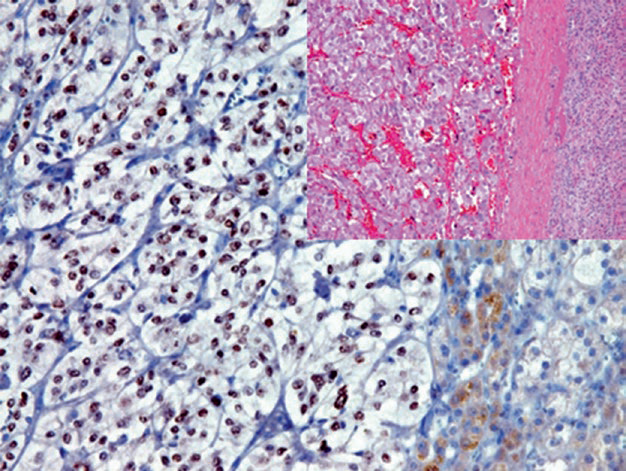

Figure 5. Pheochromocytoma, tumor cell nuclei express GATA-3.

Figure 6. A case of adrenal biopsy, neuroblastoma cell nuclei express GATA-3.